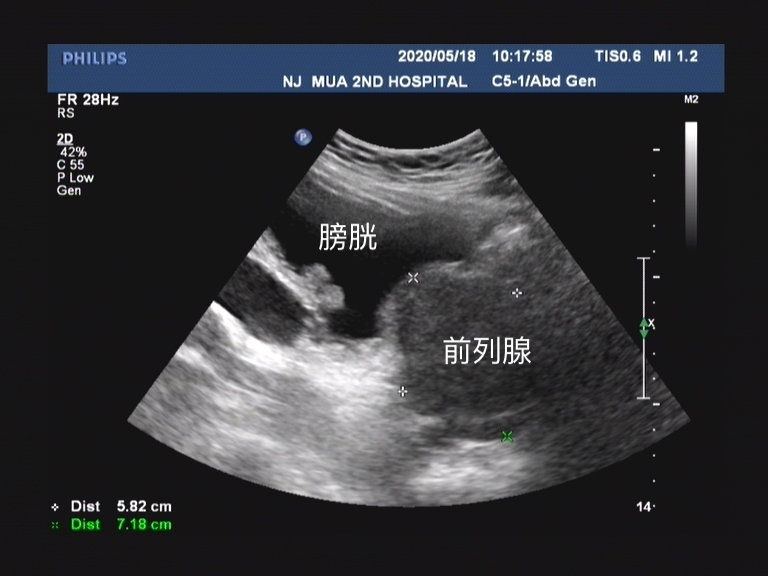

前列腺增生在中医学中属于 “癃闭” 的范畴。中成药治疗良性前列腺增生症结合了辨证论治与对症治疗, 在临床上对其症状的改善、抑制前列腺增生等方面疗效显著,优势明显。 目前临床上较为常用的中成药有以下几种,分别是: 前列康、锯叶棕果实提取物、癃清片和宁泌泰等。

总结一下,良性前列腺增生症是中老年男性的常见病、多发病。在日常诊疗中,面对种类繁多的临床用药,需要进一步规范使用方法。这些中成药不光中医在开,很多泌尿外科的西医也是在应用这些药物,所以了解每一种中成药物的具体功效,可以使患者在使用时更有针对性,有利于保证患者就诊的安全性、有效性。